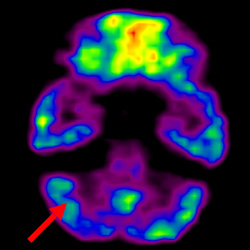

細胞治療前PET CT掃描顯示神經(jīng)組織中的藍/黑色區域,表明腦癱引起的大腦損傷。

腦癱細胞療法, 腦癱治療

細胞治療后,藍色和黑色區域減少,并且看到更活躍的區域。這表明損傷減少并改善了大腦功能。